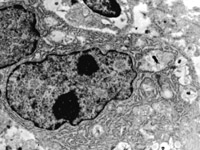

5-2-8 傷后第10天,皮膚附件上皮細(xì)胞成簇分布,核仁邊集,內(nèi)質(zhì)網(wǎng)擴(kuò)張,胞質(zhì)內(nèi)含較多張力原纖維  TEM×6000